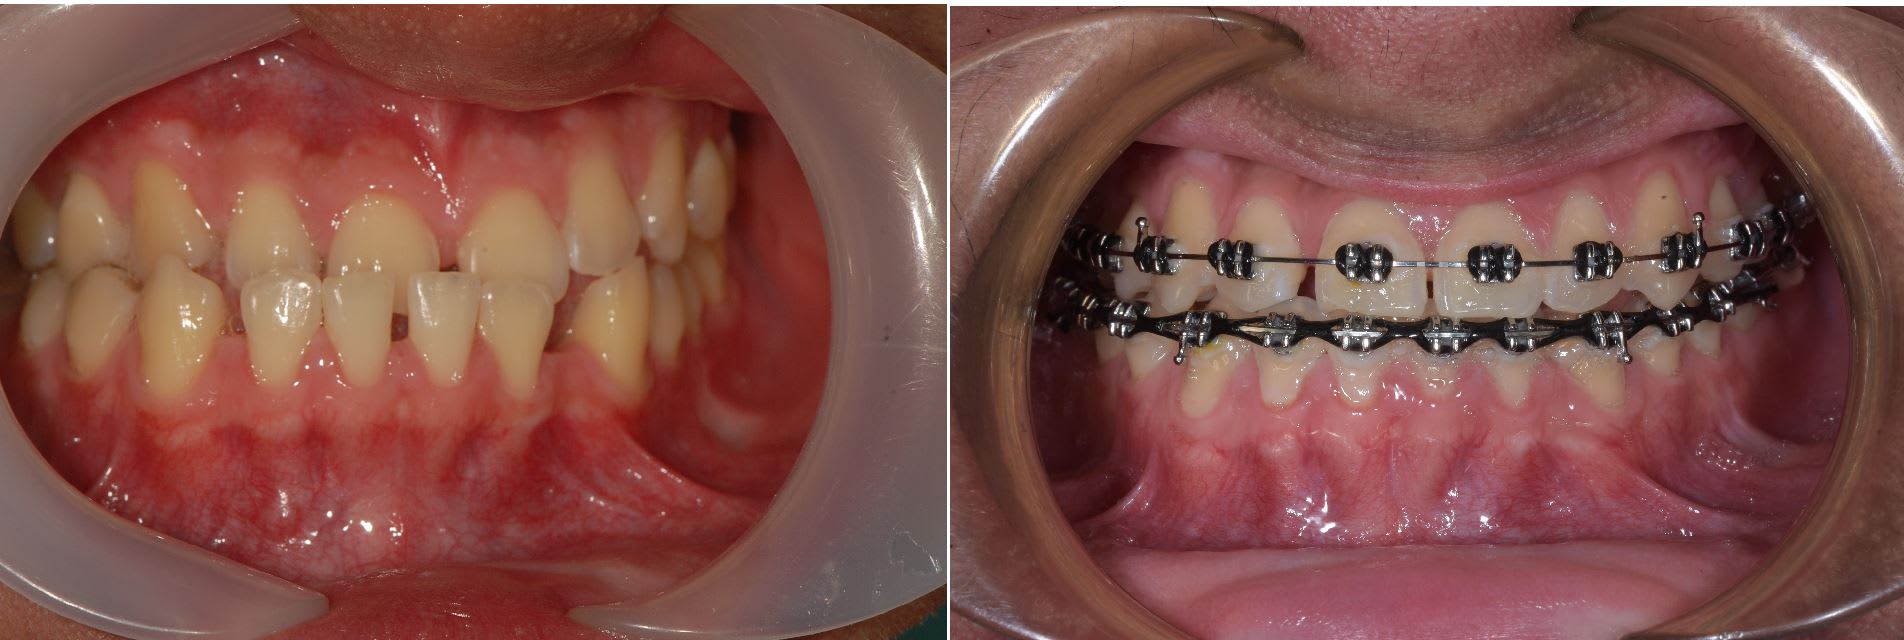

Un cas plus inhabituel Patient class III avec cross bite antérieur. Ici gros espaces en antérieur à la mandible. Vue le coté inhabituel j'ai fait un set up qui m'a indiqué qu'il fallait à la fois mésialer les secteurs postérieur supérieur et inférieure. Traduction pas de mécanique class III classique.

Pour ce patient il y a avait des espaces important à la mandibule. Visuellement je trouvais le cas inhabituel donc j'ai fait un set up 3D. Résultat il fallait mesialé à la fois à la mandibule et au maxillaire.

Une mécanique classique de class III était out ici à moins de vouloir faire sortir les incisives de la corticale.

J'ai choisie les minivisse palatine car j'ai eu de bon résultat pour mesialé avec ce type de configuration , mais je cherche encore un système prédictible à la mandibule.

La mécanique inhabituel est la raison pour laquelle j'ai présenté ce cas.

Avec une mécanique class III classique pas de stress car j'ai beaucoup de patient class III donc résultat prédictible. Ici c'était le premier patient de ce type que je traité et je n'avais jamais entendue parler de cas équivalent.

Quelque photo avant après. Les pano sont intéressante car elles montre bien que l'on à mesialé l'ensemble des secteurs post, que sa soit à la mandibule ou au maxillaire.